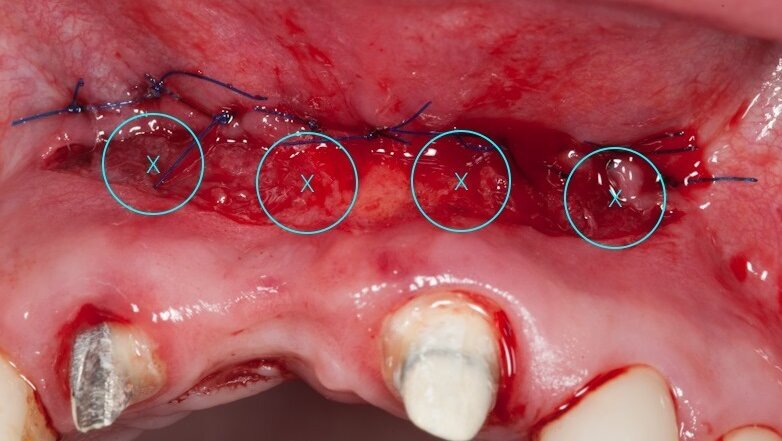

Na podstawie uzyskanych danych zasugerowano pacjentce etapowe rozwiązanie zaistniałej sytuacji, na co uzyskano zgodę. Pierwszy etap obejmował frenulotomię i westibiloplastykę w celu uzyskania poprawy zastanych warunków pod względem tkanek miękkich. Zaplanowano dowierzchołkowe przesunięcie płata śluzówkowego z pozostawieniem okostnej. Zabieg przecięcia błony śluzowej przeprowadzono przy użyciu lasera Er:YAG przy następujących ustawieniach: VLP 120 mJ, 20 Hz, a następnie przesunięty dowierzchołkowo płat błony śluzowej wraz z przyczepami mięśni przyszyto szwami materacowymi Prolene 5.0 do okostnej (Ryc. 4). Następnie, przy użyciu głowicy Genova i lasera Nd:YAG o parametrach: MSP, 0,5 W, 20 Hz dokonano naświetlenia rany w 4 miejscach po 60 s na punkt (Ryc. 5-7).

Ryc. 7_Zabieg biomodulacji w 4 punktach.